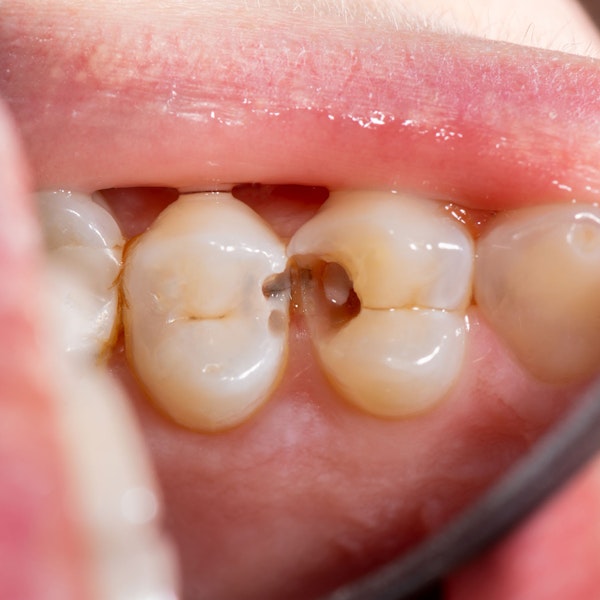

Common Warning Signs That You're Dealing with a Dental Emergency

Seeking dental care in a timely manner can prevent the need for procedures like extractions, implants, and crowns. Don't know what to look out for? If you're experiencing these symptoms, contact the team at our dental office in Warsaw, IN, immediately:

Newly-Darkened Enamel

With timely intervention, we may be able to avoid the need for an extraction altogether. We'll only choose that treatment option if we can't save your tooth.